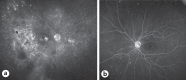

Results: A 71-year-old woman presented with a 2-month history of blurred vision in the right eye and bilateral vitreous infiltrates unresponsive to topical and systemic steroids. Vitreous biopsy of the left eye was diagnostic for lymphoma. Bulky subretinal deposits in the right eye responded to systemic therapy. The left fundus showed diffuse hypoautofluorescence and punctate, hyperfluorescent sub-retinal pigment epithelial tumor deposits, which resolved leaving hypoautofluorescent atrophic retinal pigment epithelium (RPE) scars, except inferotemporally, where retinal vasculopathy had occurred.

Conclusions: The clinical features suggest that occlusion of the inferotemporal retinal arteriole prevented sub-RPE lymphomatous deposits and subsequent RPE atrophy in this area of vascular nonperfusion. This suggests that "primary" vitreoretinal lymphoma is secondary to hematogenous spread from systemic loci. This finding, together with the ocular tumor control achieved entirely by systemic therapy, indicates scope for studies investigating systemic treatment protocols, especially those including immune-modulatory agents.